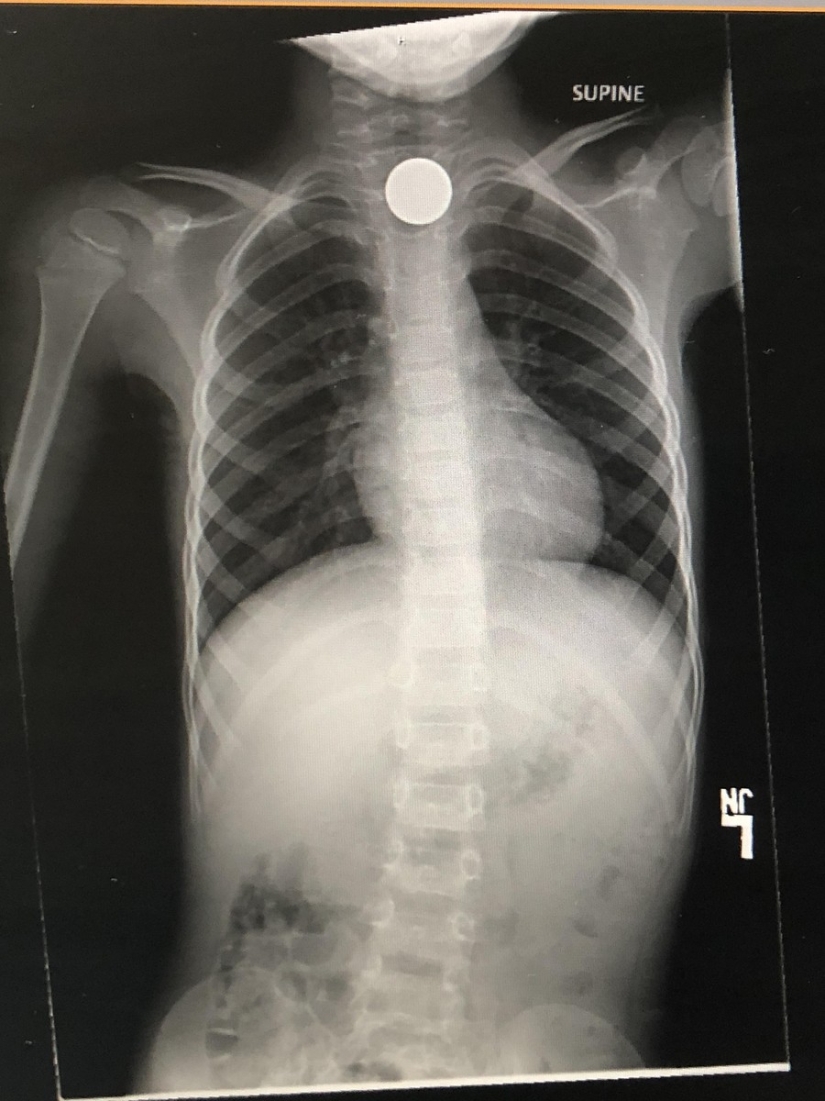

"El hijo decidió tragarse una moneda y convertir 5 centavos en 4.400 dólares de facturas médicas"